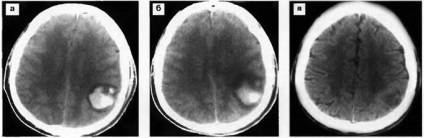

Ábra. 21. intracerebralis haematoma a bal parietális régióban. CT 3 nap (a), 7 napos (b) és 30 nap (c) traumás agysérülés után: fokozatos csökkentését a sűrűsége vérömleny, mivel a perifériás részek.